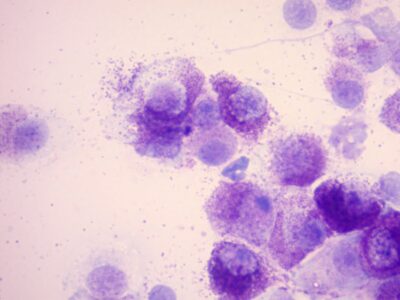

fine needle aspiration - cytology

fine needle aspiration - cytology -